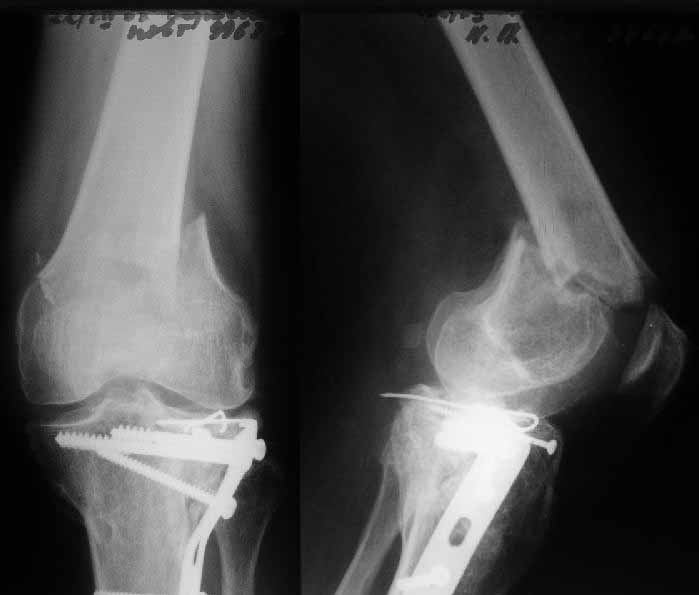

A male 52 years old was treated 1.5 years ago in our unit - ORIF of the proximal tibia. In 1 year follow-up all was OK - flexion 130, full WB, returned to work (white collar).

Two days ago he fell on a slippery sidewalk - x-rays attached. How would you manage the injury? My first thought is closed nailing. And more common question - what we should do routinely with posttraumatic local osteoporosis? When full WB and function of the extremity is restored how long does a problem of such fractures exist?

In this case a 52 year old male sustained a distal femur (supracondylar) fracture 1.5 years after plate treatment of a proximal tibia fracture which appearantly healed well. Apparently this was a low energy trauma and Alex suggests post traumatic osteopenia of the limb as a contributing or causative factor. In addition to the question of how to treat this individual patient, he poses the question how common is post-traumatic regional osteoporosis and how should it be treated or prevented and specifically is there a role for bisphosponates or somatotropins?